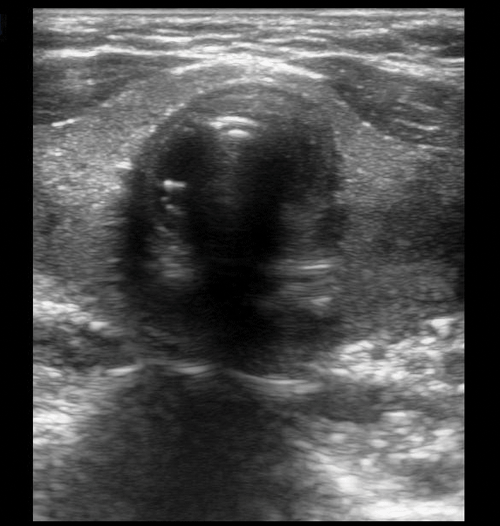

Prior to the intubation attempt, it is helpful to familiarize yourself with the important landmarks of the patient's neck, including subcutaneous tissue, thyroid tissue, and the rings of tracheal cartilage. The tracheal rings are hypoechoic, or dark. Just deep to the cartilage ring, the air-mucosal interface can be seen as a thin, hyperechoic line. Posterior to this line, the trachea is air-filled and does not transmit ultrasound waves; therefore, it appears as a dark area and the posterior structures of the airway are not visible (Figure 2). The esophagus is usually situated just posterior and to the left of the trachea. As it is usually collapsed, it is often not identified unless esophageal intubation takes place.

During intubation, the sonographer can watch as the tube passes into the trachea. Motion, similar to lung sliding, will be visible just posterior to the tracheal cartilage during intubation. This is seen as an area of increased echogenicity (Figure 3). Additionally, the sonographer should watch for the appearance of a second air-mucosal interface adjacent to the trachea, which would indicate passage of the endotracheal tube into the esophagus (Figure 4). If no second air-mucosal interface is appreciated, the tube has been correctly placed in the trachea. By performing this exam as intubation proceeds, esophageal intubation can be immediately identified prior to insufflation of the stomach.2,3